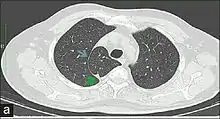

In human anatomy, an azygos lobe is a normal anatomical variation of the upper lobe of the right lung.[1] It is seen in 0.3% of the population.[2] Embryologically, it arises from an anomalous lateral course of the azygos vein,[3] in a pleural septum within the apical segment of the right upper lobe or in other words an azygos lobe is formed when the right posterior cardinal vein, one of the precursors of the azygos vein, fails to migrate over the apex of the lung and penetrates it instead, carrying along two pleural layers as the azygous fissure, that invaginates into the upper portion of the right upper lobe.[1]

An azygos lobe is usually an incidental finding on chest x-ray or CT scan. It is asymptomatic and not associated with any morbidity.[4][5] However, it can cause technical problems in thoracoscopic procedures.[6] The presence of the azygos lobe could alter the normal location of the superior vena cava or may be associated with other anomalies, including esophageal atresia or intrapulmonary right brachiocephalic veins.[7]